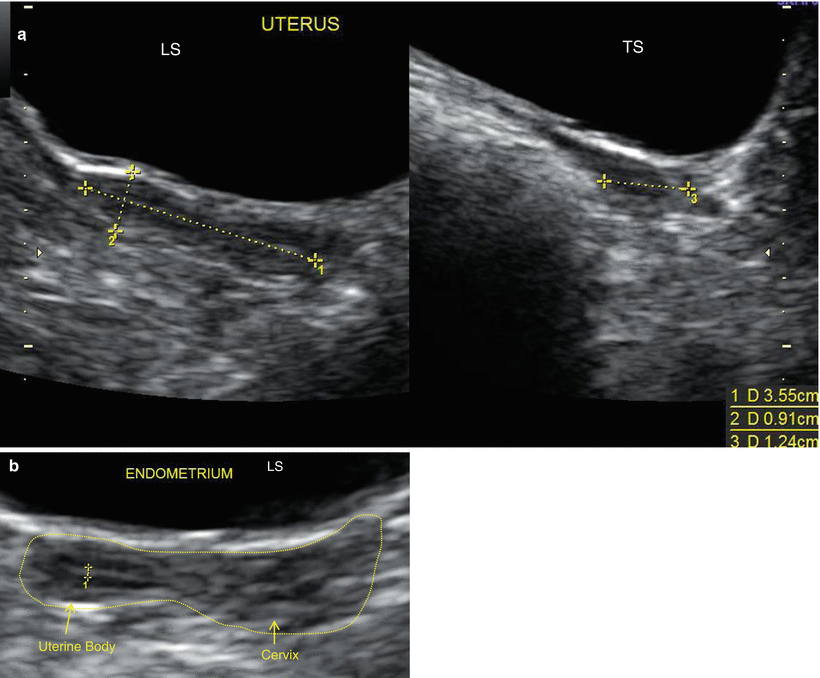

The Normal Uterus

Again, this may be calculated for the uterus as a whole or at each specific location Description of myometrial pathology (Table 1) An evaluation of myometrial pathology includes an assessment of overall myometrial echogenicity, which is reported as homogeneous or heterogeneous The reason for the heterogeneity (eg cysts, shadowing) should beWhat does a heterogeneous echotexture uterus mean Many fibroids that have been present during pregnancy shrink or disappear after pregnancy, as the uterus goes back to a normal size Risk factors There are few known risk factors for uterine fibroids, other than being a woman of reproductive age Factors that can have an impact on fibroid development include Race ;It means the texture of the uterus is not uniform on ultrasound A heterogeneous myometrial echotexture on ultrasound can be a non specific finding, of no sign Read More